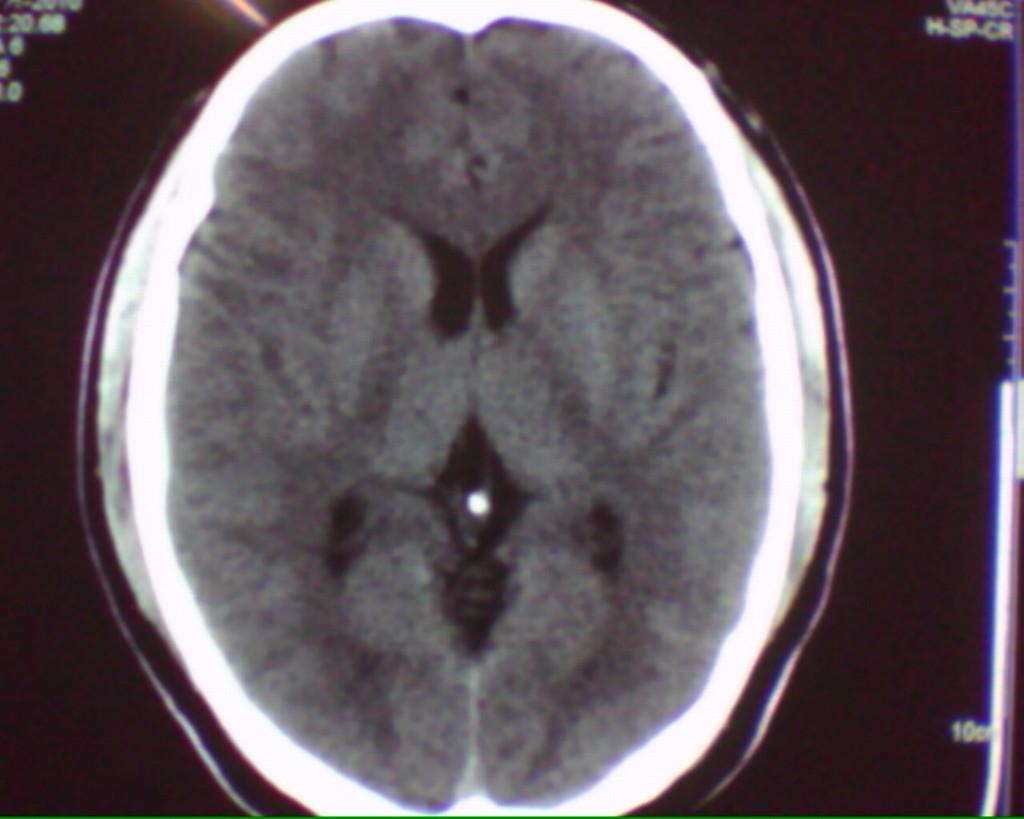

男性52岁,头部外伤,左侧眼睑及颧骨部软组织肿胀,ct发现左侧额部颅骨同板下有条状高密度影,我仔细看了一下,还是考虑伪影,主要原因是 该条状高密度影与颅骨内板有低密度影相隔,如是硬膜下或硬膜外出血,不可能出现该低密度间隔,请大家把这个病例讨论一下,谢谢。

结合自己平时遇到的病例考虑了一下,觉得还是考虑硬膜外小血肿更合适一些:首先此病人头白的位置较对称,对侧没有发现,其次受伤的部位正是此处,再次所谓的间隙如果血肿较小恐怕未必。前不久本人就遇到类似的情况,经薄层重建及随访证实确是血肿,所以建议楼主还是薄层或随访复查为上策。

我认为还是应该考虑为硬膜外薄层血肿,比较合适,放大的图像我觉得更像一些。

伪影,常见。为弧顶部分容积效应,虽然跟小血肿似乎难鉴别,但是小血肿那么大边界没有那么清楚,